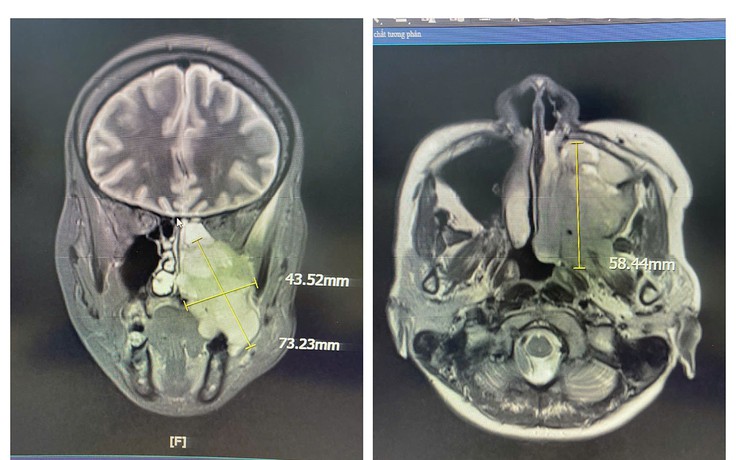

Đau hàm, nghẹt mũi, chảy máu răng - Đi khám phát hiện ung thư xoang

Liên tục bị đau vùng hàm mặt trái, nghẹt mũi, kèm chảy máu mũi và máu chân răng, người phụ nữ đi khám, bất ngờ phát hiện mắc ung thư xoang hàm - một bệnh lý hiếm gặp và khó phát hiện ở giai đoạn sớm.